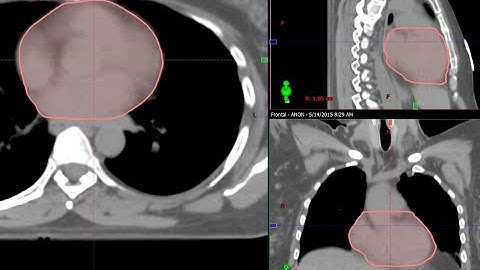

Tutorial 3 Contouring in Eclipse